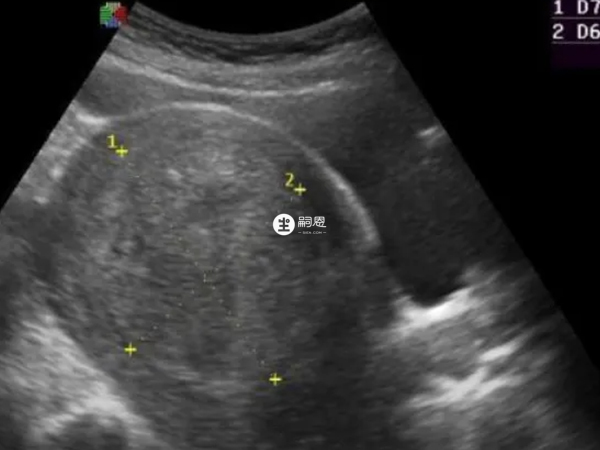

大于10厘米的子宫肌瘤非常大了,子宫变大会影响宫腔形态,让内膜表面积增大,而且超大的肌瘤也容易变性,包括恶变风险。如果不手术,大于10cm的肌瘤,就算已经绝经,也别指望它能明显缩小。加上药物治疗需长期使用,还有反弹的可能,物理治疗取不到病理,可能漏诊恶性的肌瘤,造成不良后果。所以说,大于10cm的肌瘤,不管什么年龄,有无明显症状,都建议手术治疗。

子宫肌瘤大于10厘米最好的建议就是进行手术治疗,单个肌瘤剥除就可以,不需要切除子宫。如果不做手术的话,还有两种办法,就是药物治疗和物理治疗,但药物适合长期使用,且有效缩小子宫肌瘤、停药不反弹的药物,目前是不存在的。物理治疗子宫肌瘤就是射频消融或HIFU刀,可以破坏肌瘤令其被吸收,从而达到治疗的目的。